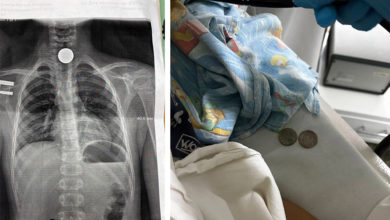

Врачи Балаково удалили гигантский камень размером 8 см из желчного пузыря

В Саратовский медицинский центр ФМБА России в Балаково поступила 53-летняя женщина с жалобами на периодические боли в правом подреберье. Как…